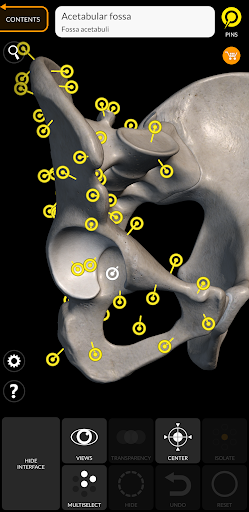

"Skeleton | 3D Atlas of Anatomy" is a next generation anatomy atlas in 3D which gives you availability of interactive highly detailed anatomical models!

Each bone of the human skeleton has been reconstructed in 3D, you can rotate and zoom in on each model and observe it in detail from any angle.

By selecting models or pins you will be shown the terms related to any specific anatomical part, you can select from 12 languages and show the terms in two languages simultaneously.

• Rotate and Zoom every model in the 3D space

• Interactive Pin allow visualization of the term relative to every anatomical detail